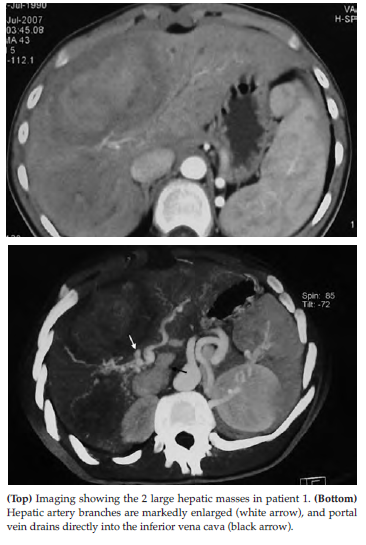

Computed tomography and magnetic resonance imaging (MRI) of the abdomen showed 2 large tumors (4 and 8 cm) in the liver; the intrahepatic branches of the portal vein could not be identified (Figure 1, top). The portal vein drained directly to the vena cava just below the level of the right inferior hepatic vein; the hepatic arteries were markedly enlarged (Figure 1, bottom). T1-weighted MRI of the brain revealed hyperintense signals in the globus pallidus, a finding that is considered compatible with hepatic encephalopathy. The Stanford-Binet intelligence scale showed moderate mental retardation (IQ 39). Biopsy of the larger mass revealed severe fibrosis and regenerative hyperplasia; however, malignancy could not be definitely excluded for the whole lesion. Although the IQ could be considered as a contraindication, the fact that he could take care of himself during intervals between encephalopathy episodes and the possibility that the shunt could be a culprit in his cognitive defect led to a decision to proceed with liver transplant.

Figure 1. Imaging Results of Abdomen in Patient 1